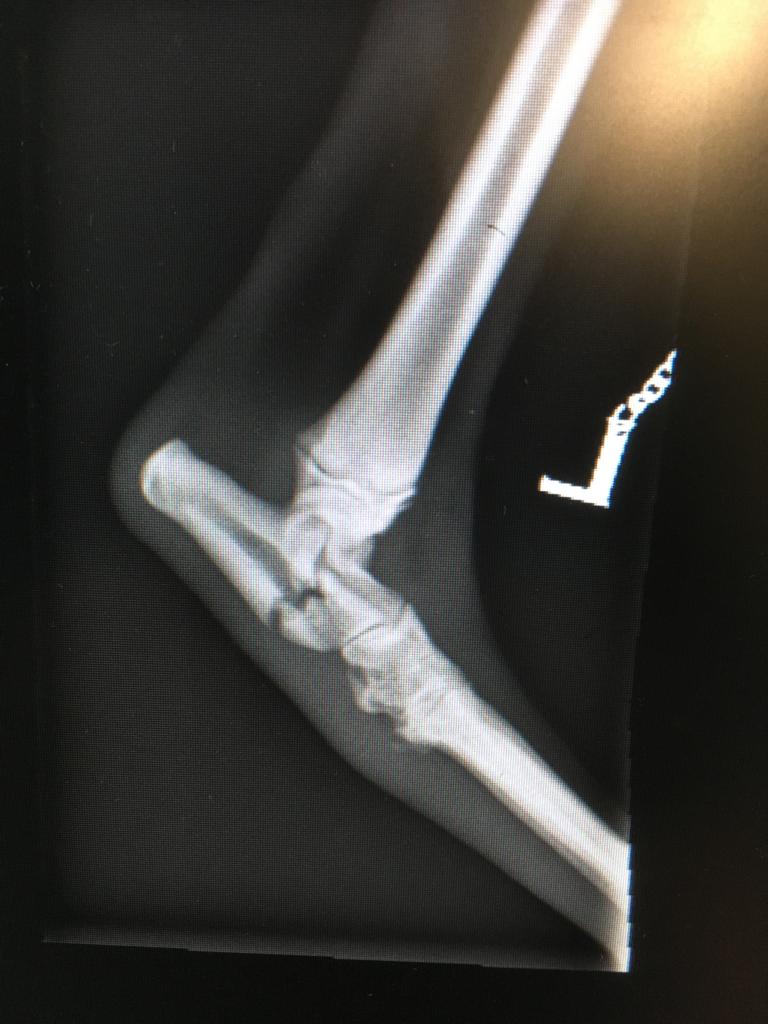

The puppy has a broken leg and I am driving her to a specialist centre in the midlands that has agreed to reduce their charges to help her. The surgeon, Jon, is then going to repair the fracture and she will come back to us for the ongoing pain relief and post operative care.